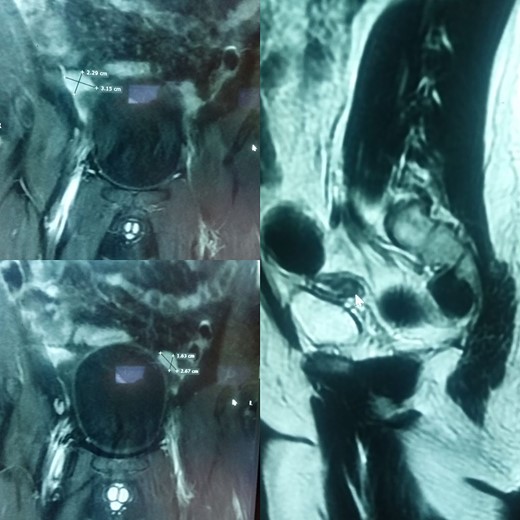

The patient and his family were counseled about the patient’s situation and were informed of the available options. A well-informed consent was obtained from him and his parents for the removal of the rudimentary uterus and both his testes. We used a laparoscopic approach to visualize the presence of testes in the right and left iliac fossas, which were attached to a rudimentary uterus, located posterior to the urinary bladder through the infundibulopelvic ligament (Fig. 2). A round ligament was also seen attaching the uterus to the abdominal wall (Fig. 3). Using the same approach, the infundibulopelvic ligament was ligated followed by the dissection of the round ligament. Uterine vessels were skeletonized and ligated. After adhesiolysis, both the testes and uterus were dissected and placed in an endobag that was then retrieved through the umbilical port and sent for histopathology (Fig. 4).

Subtotal hysterectomy and bilateral orchidopexy were performed. A tubular uterus can be seen giving off a suspensory ligament which is connecting the uterus to the testes. A coiled epididymis can also be seen attached to the testes.